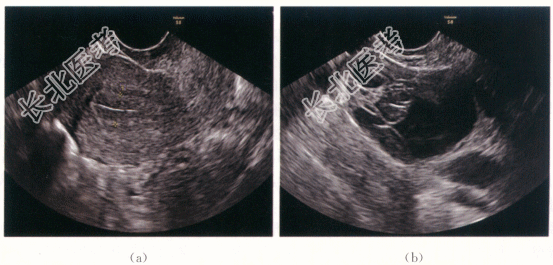

患者,女性,39岁,因“体检发现右卵巢囊性占位1年,进行性增大5个月”就诊。自诉既往无明显不适,月经规则,无腹痛,无阴道异常出血。

患者子宫前位,正常大小,活动好,无压痛;右侧附件区扪及肿块,大小5cm×3cm×4cm,质软,表面光滑,无压痛,活动度好;左侧附件区未及包块,无压痛。

CA125、CA199(-)。

- 简答题1、患者的诊断及超声依据是什么?